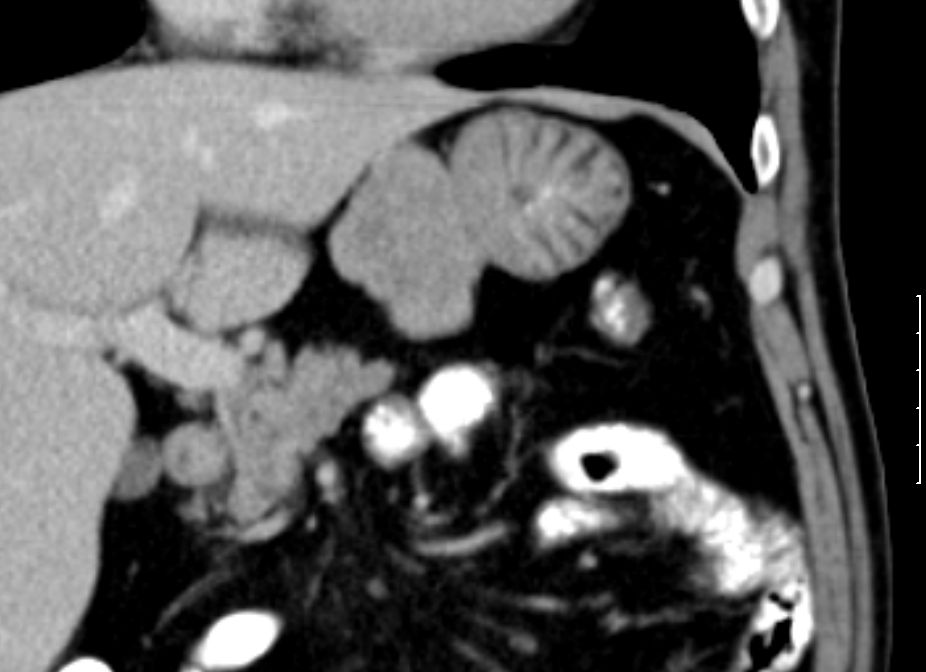

84-jährige Frau mit symptomatischer Anämie (Hb 3,8) und Kachexie (BMI 16).

Palpable Resistenz im Epigastrium.

Intraoperativ fand sich im Mesenterium des Jejunum eine 4cm große knotige Raumforderung.

Histologisch gastrointestinaler Stromatumor. Exzision im Gesunden. Ki67 = 1 % (niedriges Risiko).![]() |